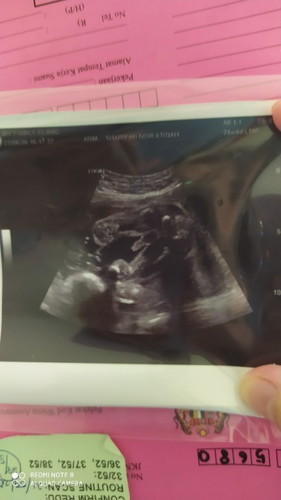

Skrang sy bru 24minggu 4harii . Hehehe.. saya lepass scan perut sya. Ehhehe. Bru ankk first. Hehehe. Tp skrngg ni sy hamill HB sy rendah 10.3 jeee HB syaa. Hmmm